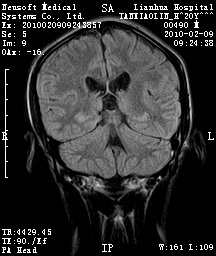

20岁男性患者,平时偶有头痛而无其他不适,现因持续头痛服药后无缓解而来院就诊。

松果体区占位继发轻度脑积水?该患者有ct资料,我已发上。

考虑松果体囊肿。

松果体囊肿?